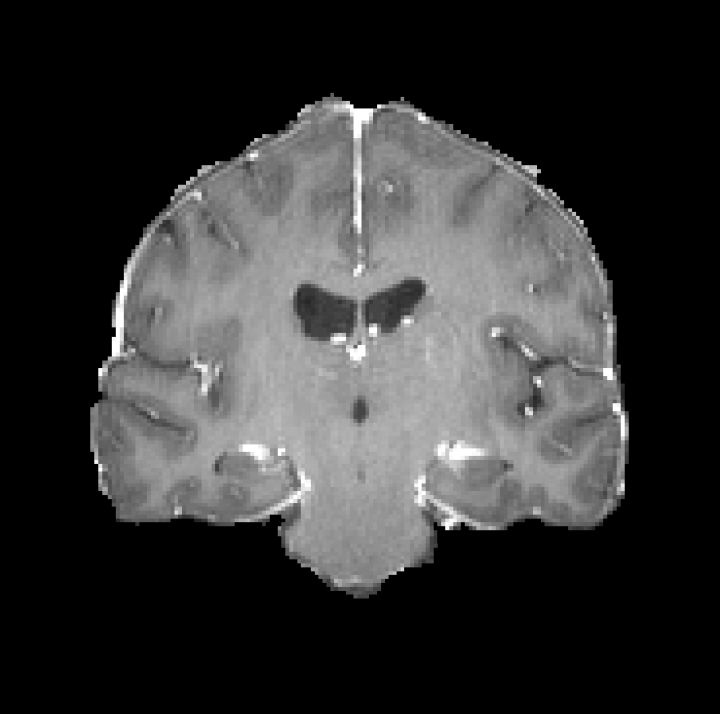

Table 7: Slice description generated by different multimodal LLMs (Blue: accurate description; red: inaccurate).

Samples (a) [Uncaptioned image] (b) [Uncaptioned image]

GPT-4Vision [18] This image is a sagittal CT scan of the human brain, providing a detailed view of the cranial structures. The cerebral cortex with its characteristic folds is clearly visible, along with the midline structures such as the corpus callosum and brainstem. The ventricles, which are fluid-filled spaces, appear as darker areas. The bright white outline represents the skull, which encases the brain. This type of scan is crucial for assessing brain abnormalities, injuries, or diseases, as it allows for a comprehensive evaluation of the brain’s anatomy and potential pathologies. This CT scan image shows an axial view of the abdomen, highlighting various internal structures. The large organ on the left side is the liver, appearing in a homogeneous gray tone. Adjacent to it, on the right, is the spleen, which is smaller and similarly shaded. The vertebral column is visible at the bottom center, appearing as a white circular structure. Surrounding tissues and organs, including portions of the intestines, are also visible, providing a detailed view of the abdominal cavity. This type of scan is essential for diagnosing abdominal conditions and assessing organ health.

Claude 3 [77] The image appears to be a medical scan, likely a CT or MRI, showing a cross-sectional view of a human brain. The brain structures are visible in shades of gray, with different densities represented. The scan appears to be focused on a specific region of the brain, revealing intricate details of the anatomy. Medical professionals would use this type of image to analyze the brain’s structure and identify any potential abnormalities or pathologies that may require further examination or treatment. This medical image appears to be a cross-sectional computed tomography (CT) scan of the abdomen. The image shows a detailed view of the internal structures, including the liver, spleen, and other abdominal organs. The high-contrast, black and white image provides a comprehensive representation of the anatomical features, allowing for the identification and examination of various organs and tissues. This type of imaging is commonly used in medical diagnosis and treatment planning for conditions affecting the abdominal region.

HuatuoGPT-Vision-7B [78] The image shows a sagittal view of the brain, which appears to be normal in structure and anatomy. The cerebral cortex, ventricles, cerebellum, and other key structures are clearly visible without any obvious abnormalities or pathological findings. This suggests that this is likely an unremarkable CT scan of the head taken after some form of treatment or intervention, as indicated by the reference information provided. The image shows a computed tomography (CT) scan of the abdomen, which reveals an enlarged liver with multiple hypodense lesions throughout both lobes. These findings are consistent with metastatic disease involving the liver parenchyma and peritoneal surfaces. The CT scan provides detailed anatomical information that can be used to assess the extent and distribution of the hepatic lesions for further clinical evaluation and management.